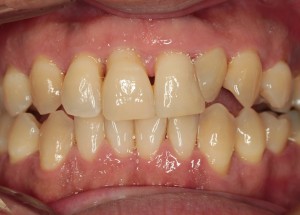

治療後の歯ぐき

きれいなピンク色の引き締まった歯ぐき

歯周病の治療を行い、噛み合わせを整えて、最終的なかぶせものでつなげて歯を守っています。

健康的な引き締まったピンク色の歯ぐきになっています。